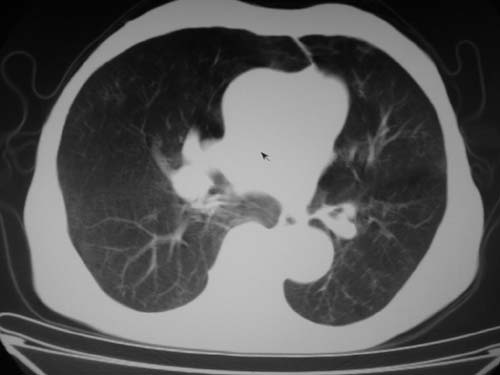

标题: CT19736:男,76岁,咳嗽,胸痛 [打印本页]

标题: CT19736:男,76岁,咳嗽,胸痛

支持左上肺周围型肺癌性并空洞形成伴胸椎转移。

支持 左上肺周围型肺癌性并癌性空洞形成伴胸椎转移。

支持左上肺周围型肺癌并空洞形成伴胸椎转移。z左下肺炎

左上肺癌性空洞伴胸椎转移。